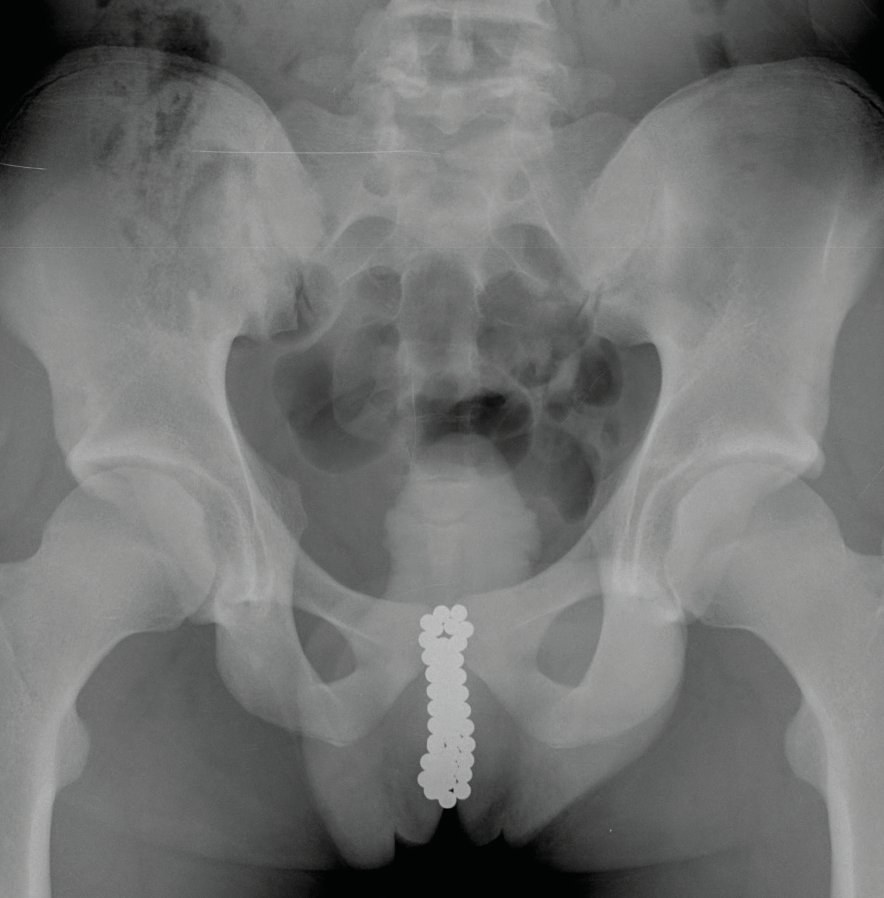

Are buckyballs illegal to buy outlet, The Pull of Buckyballs A Teen s Urethral Insertion of Strong outlet

The Pull of Buckyballs A Teen s Urethral Insertion of Strong

The Pull of Buckyballs A Teen s Urethral Insertion of Strong